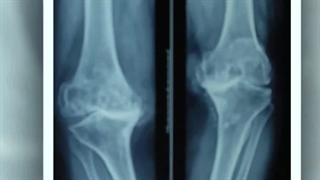

چه مدت بعد از پروتز زانو راه برویم؟

چند وقت بعد از پروتز زانو راه برویم؟